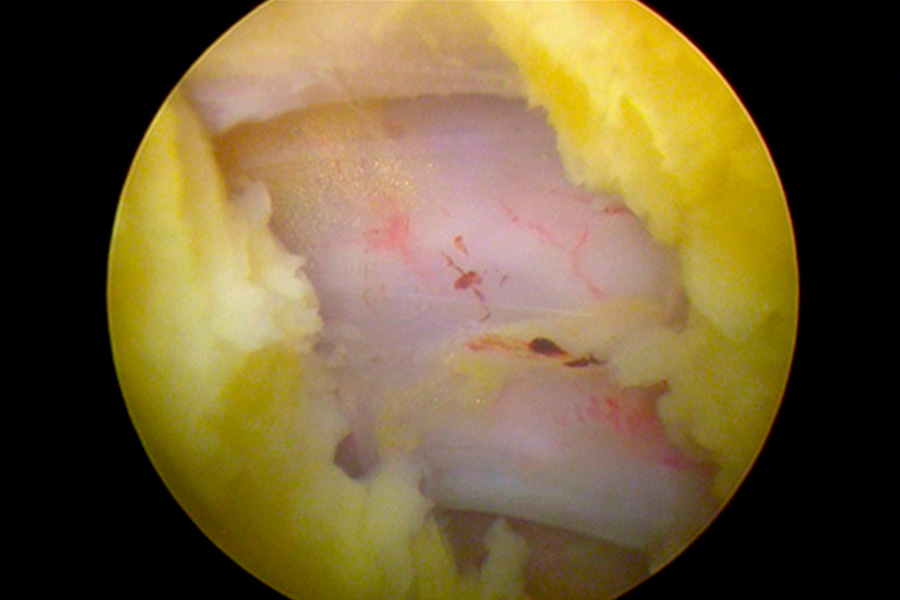

Caso clínico: endoscopia de columna multinivel L4L5 y L5S1

Durante la intervención quirúrgica, se abordarán los dos niveles mediante la técnica de endoscopia de columna.